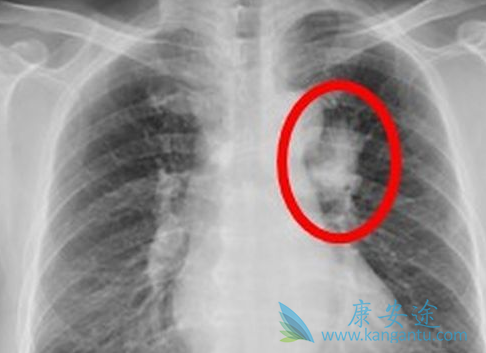

对于发病率和死亡率双高的肺癌来说,化疗也是其治疗的一个非常重要的手段,尤其是对小细胞肺癌来说,化疗是主要的治疗手段。相应的化疗也有很多副作用,临床上经常会有患者家属担心化疗副作用大,家人身体无法承受。那么在临床中是如何评估患者的体质能否耐受化疗呢?大多数情况下,患者需要一般状况较好,血象和肝肾功能正常才能耐受抗肿瘤治疗。下面阐述临床中常见的肺癌化疗不良反应呕吐及处理: